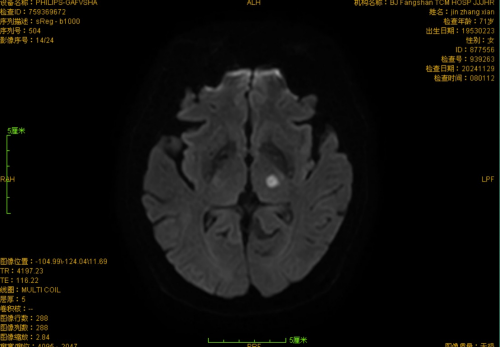

近日,一例75岁老年女性,以“右口周、右手指麻木2小时余”为主诉患者就诊于我院急诊,经卒中团队评估,考虑“丘脑梗死”,存在出现“丘脑共济失调综合症”风险,重者可致轻偏瘫,综合考虑,建议患者静脉溶栓治疗,经急诊-脑病卒中绿道联合救治,患者溶栓后右口周、右手指麻木症状消失,经住院治疗7天痊愈出院。

该类患者基本上均以口周、手足麻木起病,后续病情进展可出现偏侧共济失调和轻瘫。影像学结果均提示:丘脑新发脑梗死;既往一般认为,丘脑梗死多对患者感觉系统影响较大,未见波及共济及肌力的患者。卒中团队发现确实有文献报道丘脑腹外侧梗死所致“手口综合症”“手口足综合症”、“丘脑共济失调综合症”、“丘脑共济失调轻偏瘫”等,可能与其损伤小脑环路有关,主要责任血管归属于大脑后动脉P2段,属于后循环梗死的一种,存在致残风险;学习讨论后我们得出对仅表现为手足麻木的患者,尤其伴口周麻木者,如排除其他疾病,考虑急性脑梗死,无禁忌症应建议积极溶栓治疗、防止卒中进展致残的结论,这才有了此次救治成功的病例。